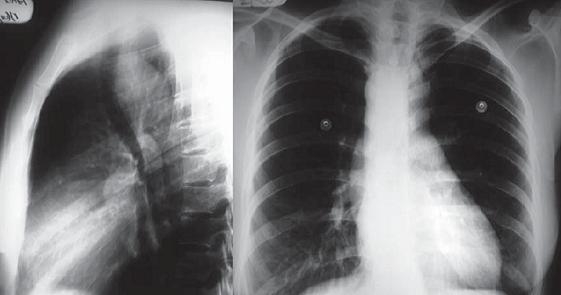

An initial upper endoscopy, an esophagogram, and an x-ray of the thorax were performed. The endoscopy showed no alterations, while the esophagogram showed lateralization of the esophagus toward the left through the aortic arch and the descending aorta, but no other findings (figure 1). The thorax x-ray showed mediastinal widening and curvature of the tracheal air column on the superior mediastinum with a posterior correction in its distal route (figure 2). Based on these results the decision was made to proceed with an enhanced contrast thorax CT scan. This scan showed an anatomical variation: a right aortic arch was present with an aberrant left subclavial artery running around the trachea and esophagus with variants in the carotid arteries (figure 3). To achieve a better description of these alterations magnetic angioresonance of the thorax was performed. It confirmed the tomographic findings and showed a dilatation at the end of the aortic arch (Kommerell's diverticulum) which is the point of origin of the aberrant left subclavial artery. It also showed a common point of origin for the common carotid arteries (bicarotid trunk) (figure 4). The patient was evaluated again following these results (nine months after onset of symptoms). Symptoms persisted with the same frequency and intensity as at her first visit to our services. No new symptoms had developed. Consequent to these findings she was referred to vascular surgery for a determination regarding the need for surgery. This evaluation is pending as of this writing.Figure 1. Esophagram showing displacement of esophagus to the left secondary to the location of the aortic arch and descending aorta.

Figure 2. A. Lateral projection radiograph of the chest. B. Posteroanterior projection radiograph of the chest in which mediastinal widening (due to the presence of right descending aorta) can be seen. The aortic button over the midline and backward displacement of the air passage of the trachea in the upper mediastinum with posterior normalization in its distal trajectory can be seen.